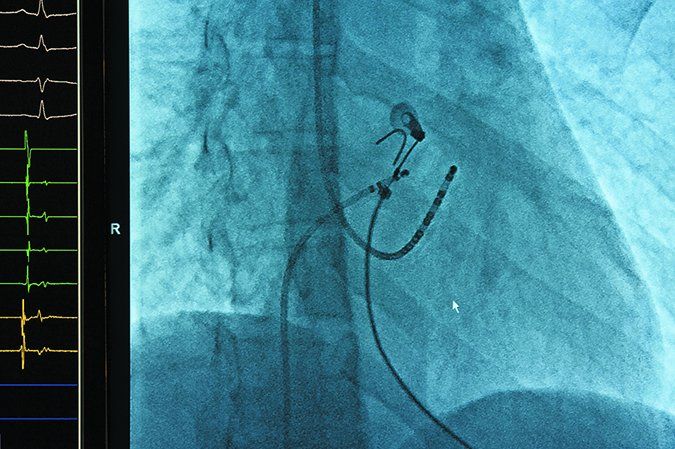

Atrial fibrillation affects an estimated 10 percent of Americans 65 and older. It develops when there is a disruption to the usual electrical activity in the heart that keeps it pumping in a healthy rhythm. Electrical signals in the atria become chaotic and unpredictable, causing the heart to beat in an erratic manner. This reduces the pumping efficiency of the heart and raises the risk of blood pooling in the heart and forming a clot. A blood clot that exits the heart can make its way to the brain and cause a stroke.